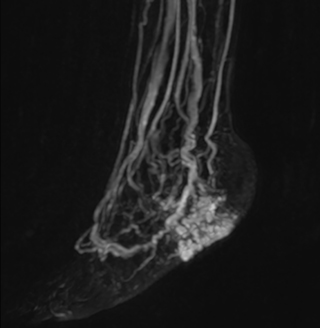

MRA run-off study with mDIXON

The subtractionless peripheral MR angiography shows improved vessel-to-background contrast and high resolution. Ingenia Ambition 1.5T.

Station

Ingenia Ambition

Pelvis

Voxels 1.3 x 1.3 x 3.2 mm, FOV 430 mm, 125 slices

Upper legs

Lower legs

Voxels 1.0 x 0.82 x 2.0 mm, FOV 430 mm, 125 slices